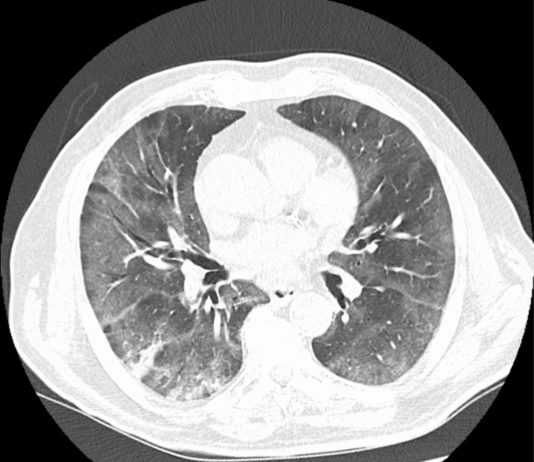

87-years old male

patient with HTA, chronic cardiomyopathy was hospitalized from February 27 to

March 1, 2020 for right-sided heart failure...